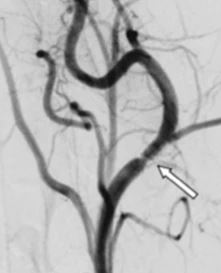

The authors investigated proprietary antithrombogenic coatings applied to flow-diverter stents (FDSs). The in vivo experiments showed that HPC-coated p64 FDSs appeared to be biocompatible.

Article: In vivo canine study of three different coatings applied to p64 flow-diverter stents: initial biocompatibility study